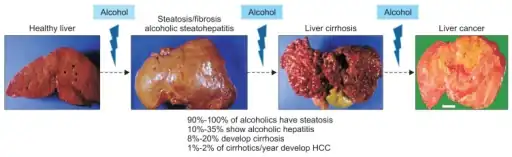

Cirrhosis

In addition to virus-related cirrhosis described above, other causes of cirrhosis can lead to HCC. Alcohol intake correlates with risk of HCC, and the risk is far greater in individuals with an alcohol-induced cirrhotic liver. There are a few disorders that are known to cause cirrhosis and lead to cancer, including hereditary hemochromatosis and primary biliary cirrhosis.[21]

Progression for alcoholic liver injury to steatosis with scarring, and architectural distortion leading to cirrhosis; as a complication of cirrhosis, hepatocellular carcinoma may occur

Progression for alcoholic liver injury to steatosis with scarring, and architectural distortion leading to cirrhosis; as a complication of cirrhosis, hepatocellular carcinoma may occur